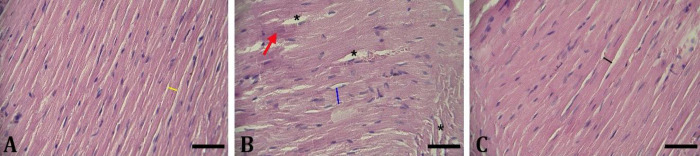

Cardiac mitochondrial dysfunction is an important feature of aged heart. However, there is still no potent agent to ameliorate cardiac function abnormalities in aged hosts. Olive oil (OLO), containing monounsaturated fatty acids, has diverse protective effects on the cardiovascular system, including anti-diabetic, anti-inflammatory, and anti-hypertensive effects. We evaluated the beneficial impacts of OLO against aging-related cardiac dysfunction. Wistar rats were randomly allotted into three groups with eight rats, including control, aged rats receiving D-galactose (D-GAL), and aged rats administrated with D-galactose plus OLO (D-GAL + OLO). Aged animals were received D-GAL at a dose of 150.00 mg kg-1 daily through intra-peritoneal injection for aging induction. The animals in D-GAL + OLO group were co-administrated with oral OLO at a dose of 1.00 mL kg-1 by gavage feeding daily. The administration term was eight weeks. A histological examination of heart tissue was performed. The heart tissues were also harvested to assay the oxidative stress and molecular parameters. The aged animals showed cardiac hypertrophy, increased malondialdehyde level and Bax expression, and reduced mitofusin 2, phosphatase and tensin homologue-induced putative kinase 1, dynamin-related protein 1, and Bcl2 expressions in comparison with the control animals. The OLO treatment ameliorated all these parameters. Overall, OLO could improve cardiac aging through reducing oxidative stress, enhancing genes mediated mitophagy, and improving genes mediated apoptosis in the heart.